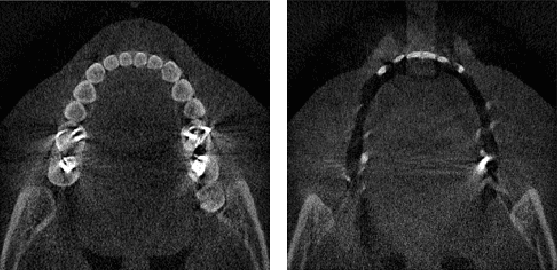

Metal artifact reduction (MAR) is one of the most important research topics in computed tomography (CT). With the advance of deep learning technology for image reconstruction,various deep learning methods have been also suggested for metal artifact removal, among which supervised learning methods are most popular. However, matched non-metal and metal image pairs are difficult to obtain in real CT acquisition. Recently, a promising unsupervised learning for MAR was proposed using feature disentanglement, but the resulting network architecture is complication and difficult to handle large size clinical images. To address this, here we propose a much simpler and much effective unsupervised MAR method for CT. The proposed method is based on a novel beta-cycleGAN architecture derived from the optimal transport theory for appropriate feature space disentanglement. Another important contribution is to show that attention mechanism is the key element to effectively remove the metal artifacts. Specifically, by adding the convolutional block attention module (CBAM) layers with a proper disentanglement parameter, experimental results confirm that we can get more improved MAR that preserves the detailed texture of the original image.